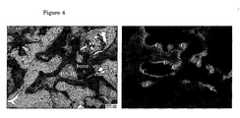

- Fig. 4Left, bone induction in 40CaP after 12 weeks of intramuscular implantation.Right, fluorescent image showing that bone formation started between 6 and 9 weeks after implantation (C, calcein).

Porous blocks (7x7x7 mm, n=7 per material) were implanted in paraspinal muscle of 7 dogs for 12 weeks. Tetracycline, xylenol orange and calcein were intravenously injected 3, 6 and 9 weeks after implantation, respectively. Harvested samples were fixed in 4% buffered formaldehyde at 4°C for 1 week, dehydrated with a series of ethanol solutions (70%, 80%, 90%, 95% and 100% per 2 times each, 3 days each step) and embedded in methylmetacrylate and non-decalcified histological sections (10-20 µm) were made. Sections for light microscopic observations were stained with 1% methylene blue and 0.3% basic fuchsin solutions, while unstained sections were used for fluorescent microscopic evaluations. At retrieval the implants were surrounded by a layer of connective tissue and a limited inflammatory reaction was observed. 40 CaP retained its shape and the pores were filled with

de novo bone tissue (n=70, which was directly formed on the material surface (

Fig. 3). In other material (0 CaP, 10 CaP, 20 CaP no bone formation was detected. Histomorphological results are summarized in Table 1. Fluorescence microscopy showed that bone formation in 40 CaP started between 6 and 9 weeks after implantation (

Fig. 4). The 40 CaP implants retained their shape, while the other implants lost their shape and porous architecture. Moreover, from histological images it was observed that the material degrades, and that mechanical strength increased with apatite content, since 40 CaP kept its shape for 12 weeks.